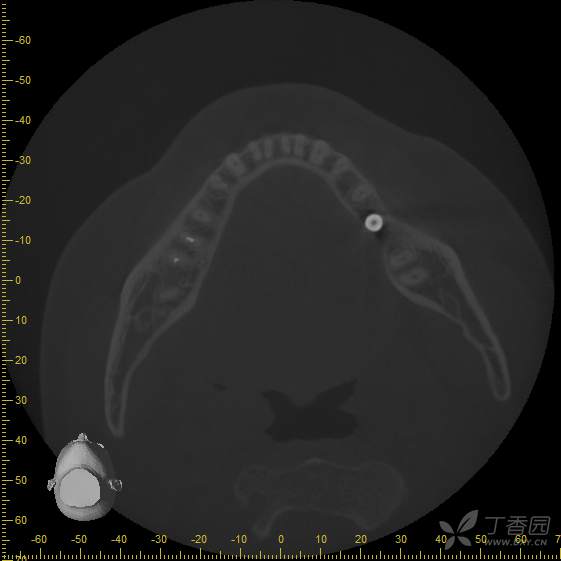

手术即刻拍摄cbct,手术过程中刮净肉芽组织,碘酊灼烧,大量生理盐水冲洗,植入4.8*8mm骨水平种植体一枚

接诊时,36种植牙松1-2°,颊侧牙龈未见明显红肿。拍摄cbct后可见种植体周骨结合丧失,大量低密度影,骨吸收至根尖1/3,种植体浮出。